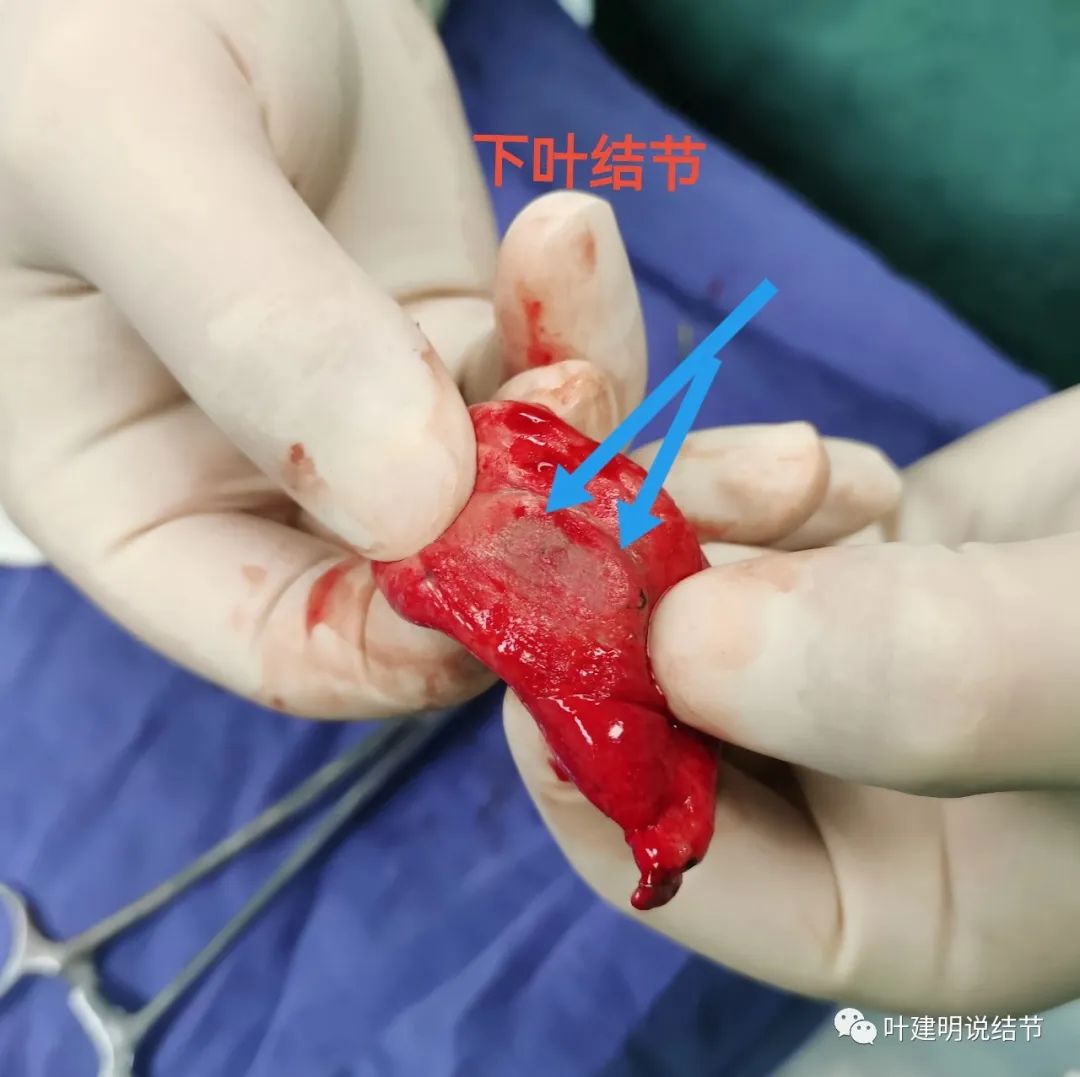

下叶病灶8,予以局部楔形切除。

确实如术前判断,上叶尖段病灶2、后段病灶6与下叶灶8是原位腺癌,中叶病灶9是浸润性腺癌,贴壁占10%,腺泡型占90%。切缘均阴性。